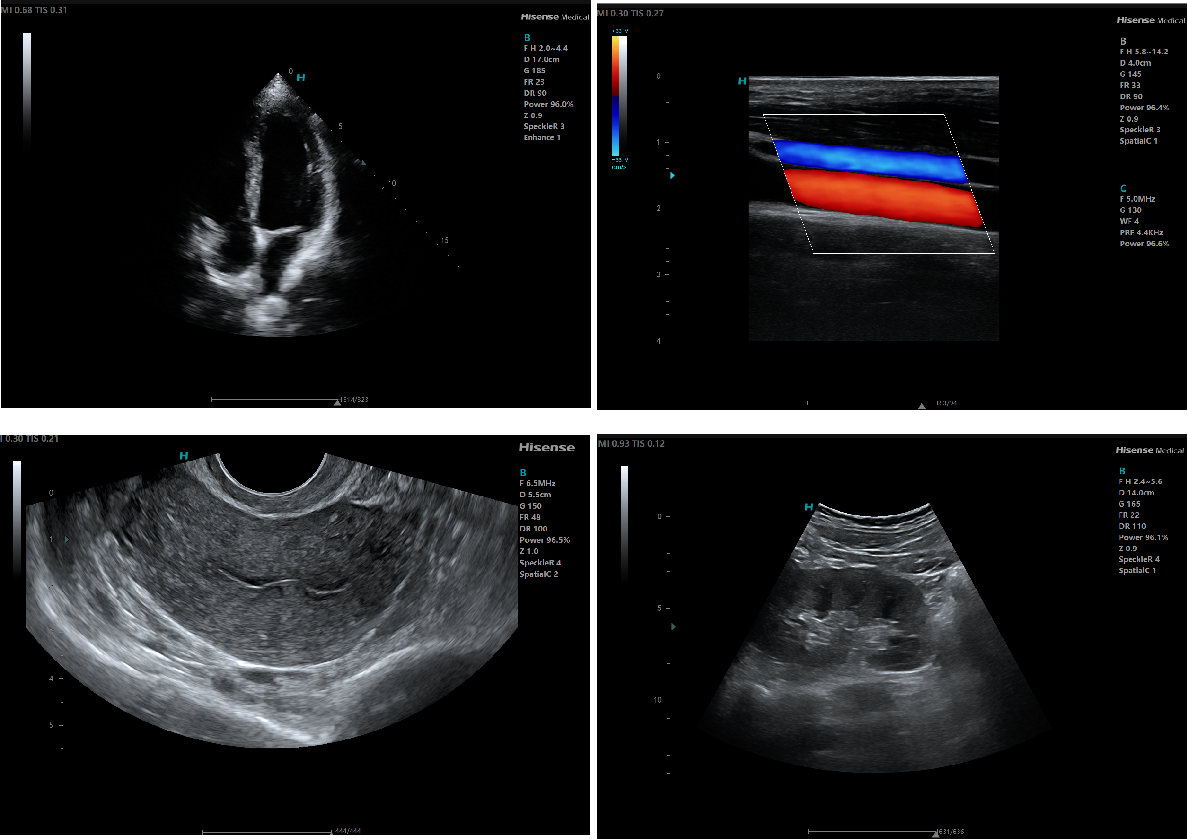

Clinical Imaging

Continuous probe innovation ensures high-quality imaging across applications.